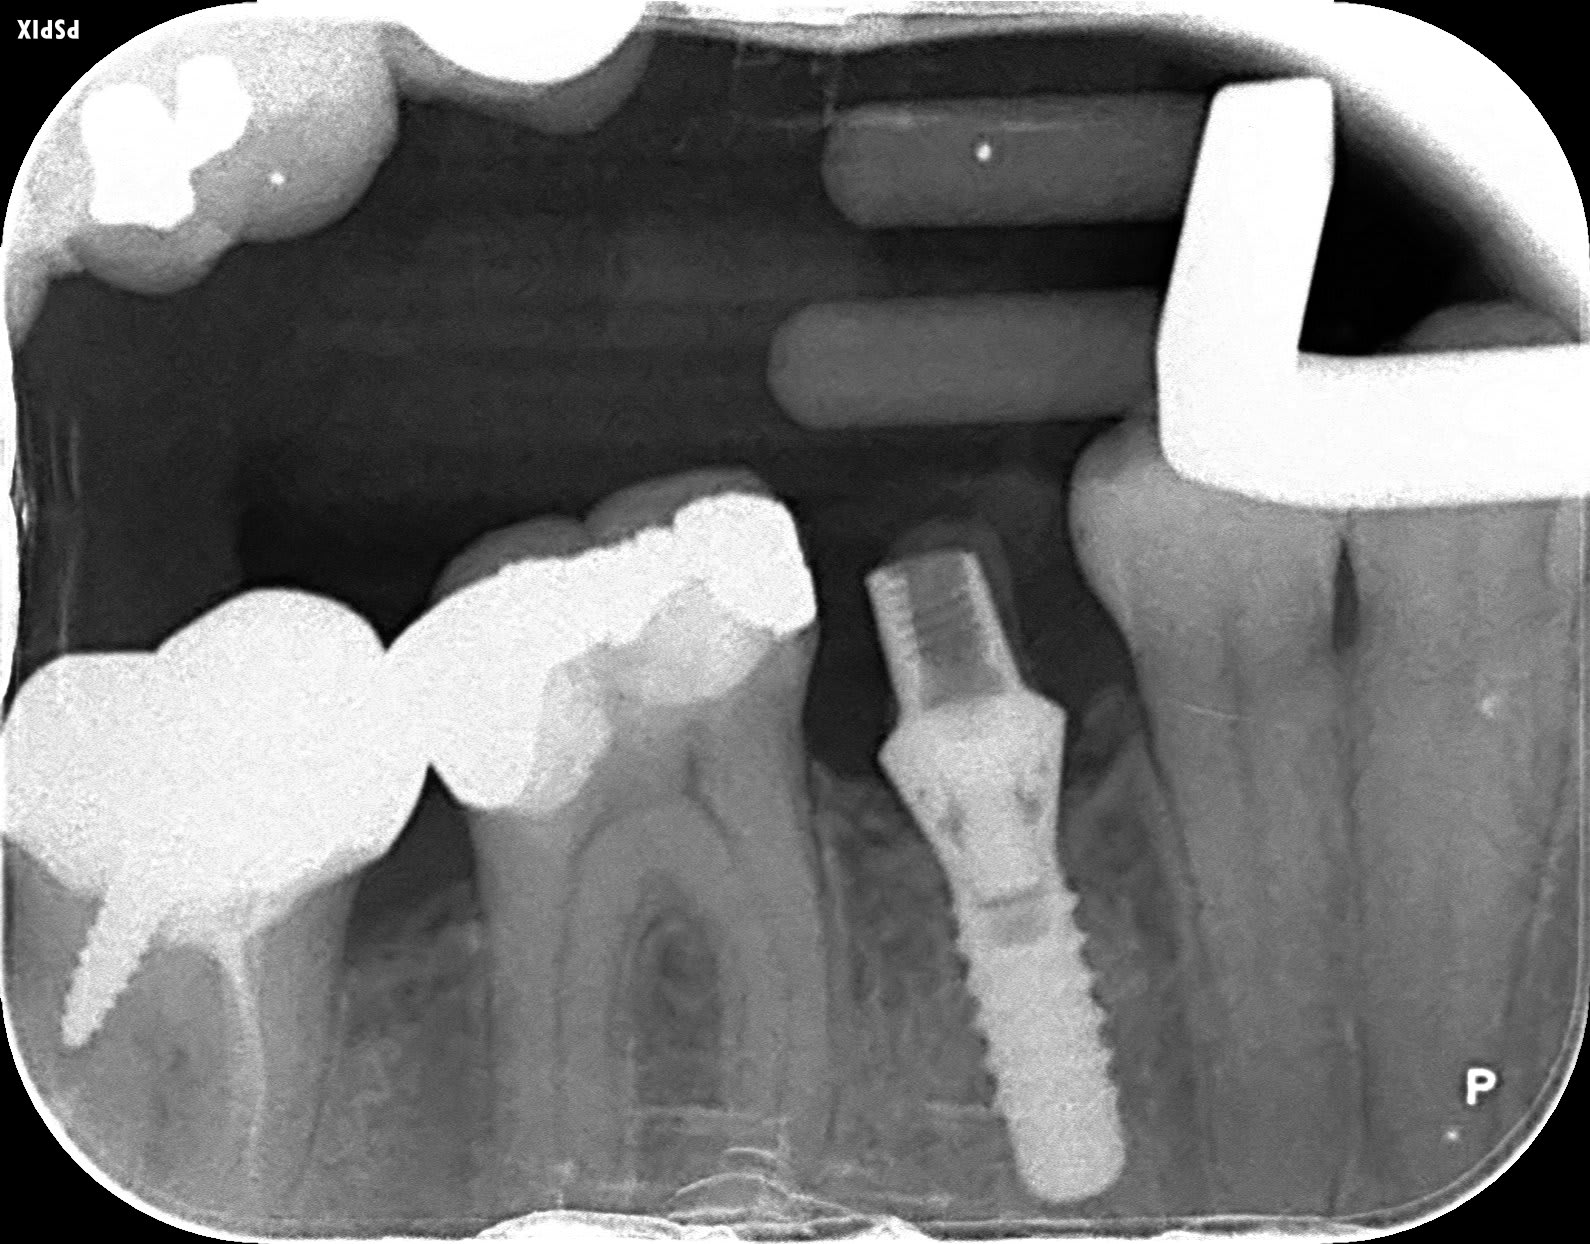

quel implant ?

Bonjour j'aimerai avoir votre avis sur la marque de cet implant posé chez une patiente qui aimerai changer sa couronne provisoire en place depuis quelques années...

straumann RN?

http://whatimplantisthat.com/implant/standard-plus-rn/

C'est bien un straumann 100 %sur